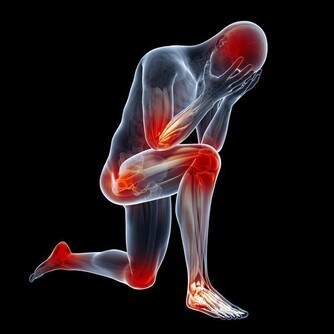

血管阻塞是長年累月的結果,最初發生問題的「徵兆」是什麼呢?腳是人體的末梢,也是心臟最遠端,血管有問題,腳最先有感覺。

因此血管阻塞的最初有兩個症狀,一是腿開始怕冷,二是走較久的路時,只有一邊的腿容易疲勞酸痛。

當血管阻塞情況加重,就會出現一種奇怪的狀況——間歇性跛行。

比如有些老人家,走了2站路就感覺走不動了,腿酸痛,休息一會,又能走了是典型的血管動脈阻塞的癥狀,血管性性間歇性跛行。

這種酸痛,不是來源於關節疾病,而是源自肌肉酸痛,主要就是因為肌肉運動需要耗氧量大,而血管沒有及時供給造成的酸痛。